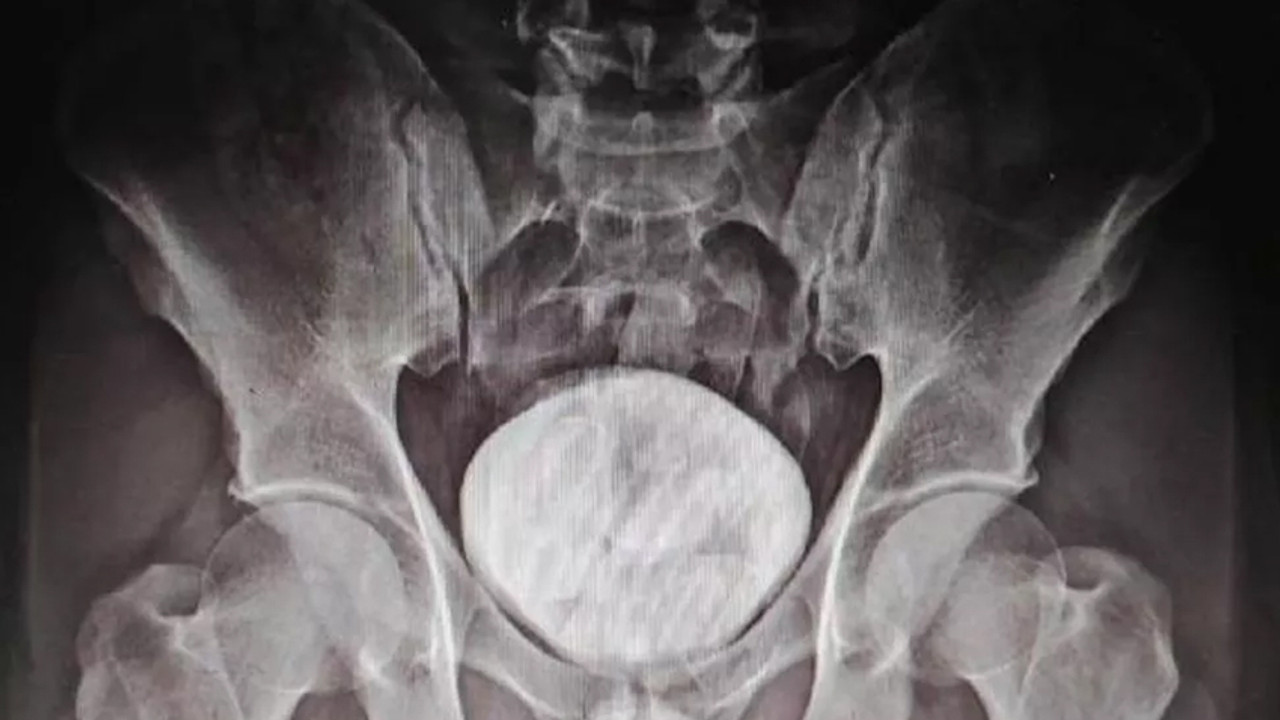

RÖNTGENDE TESPİT EDİLDİ

Kars Harakani Devlet Hastanesi’ne götürülen Tazehkand’ın çekilen röntgeninde, makatında uyuşturucu tespit edildi. Uyuşturucuyu doğal yollardan çıkaran Tazehkand, gözaltına alındı. Emniyetteki işlemlerinin ardından adliyeye sevk edilen şüpheli, çıkarıldığı hakimlikçe tutuklandı.